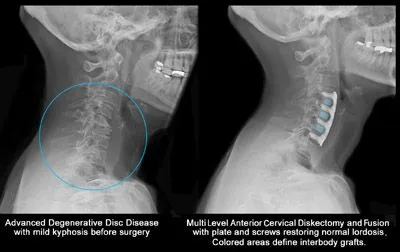

These x-rays are necessary to possibly detect a problem that is non-neuromuscular, such as cancer, broken bones or other types of maladies that may hinder the progress if orthodox chiropractic care were begun.